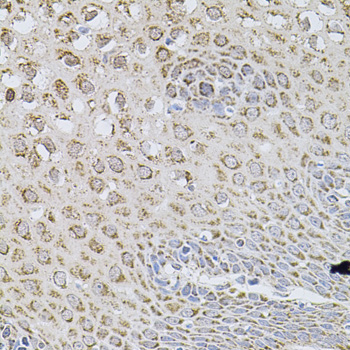

Immunohistochemistry of paraffin-embedded rat brain using WISP2 at dilution of 1:100 (40x lens).

,

Immunohistochemistry of paraffin-embedded human esophagus using WISP2 at dilution of 1:100 (40x lens).

Immunohistochemistry of paraffin-embedded human stomach using WISP2 at dilution of 1:100 (40x lens).

Immunohistochemistry of paraffin-embedded mouse brain using WISP2 at dilution of 1:100 (40x lens).

应用详情:WB 1:500 - 1:2000

IHC 1:50 - 1:100

IF 1:50 - 1:100